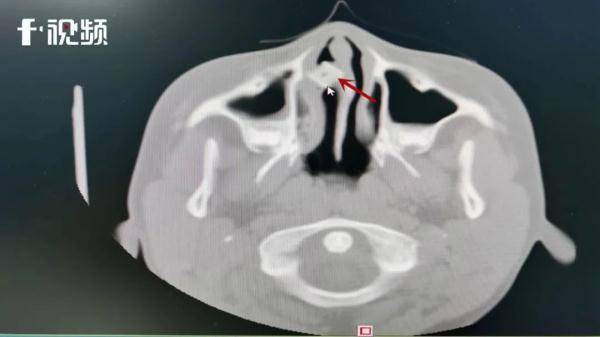

▲小邓鼻腔内发现明显异物

完善相关检查后,医生在小邓鼻腔内发现明显异物,且异物周围已长满肉芽引发了感染。

“给患者做了个前鼻镜检查,明显看到鼻腔有肿块,且肿块边缘被肉芽包裹,经过进一步检查发现,异物卡在患者下颌窦窦口位置,异物形状类似方形色子,手术取出发现是一个打麻将用的色子。”刘刚表示。